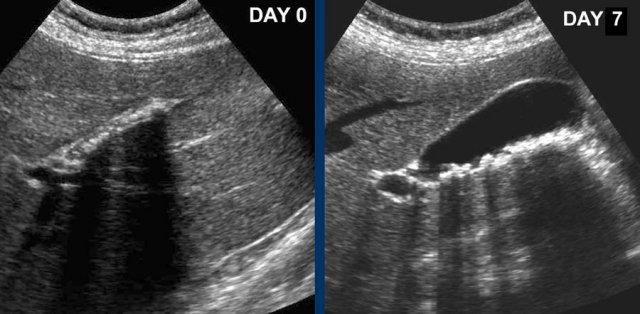

Vào ngày 0, có phù nề túi mật cấp tính do sỏi bị kẹt.

Một ngày sau, bệnh nhân không còn triệu chứng.

Sỏi vẫn còn tại chỗ, nhưng rõ ràng cho phép mật lưu thông qua ống túi mật, vì phù nề đã biến mất.

Phù nề tái tưới máu và bùn mật là những dấu hiệu chứng nhân thầm lặng của cơn đau trước đó.

CRP vẫn bình thường.